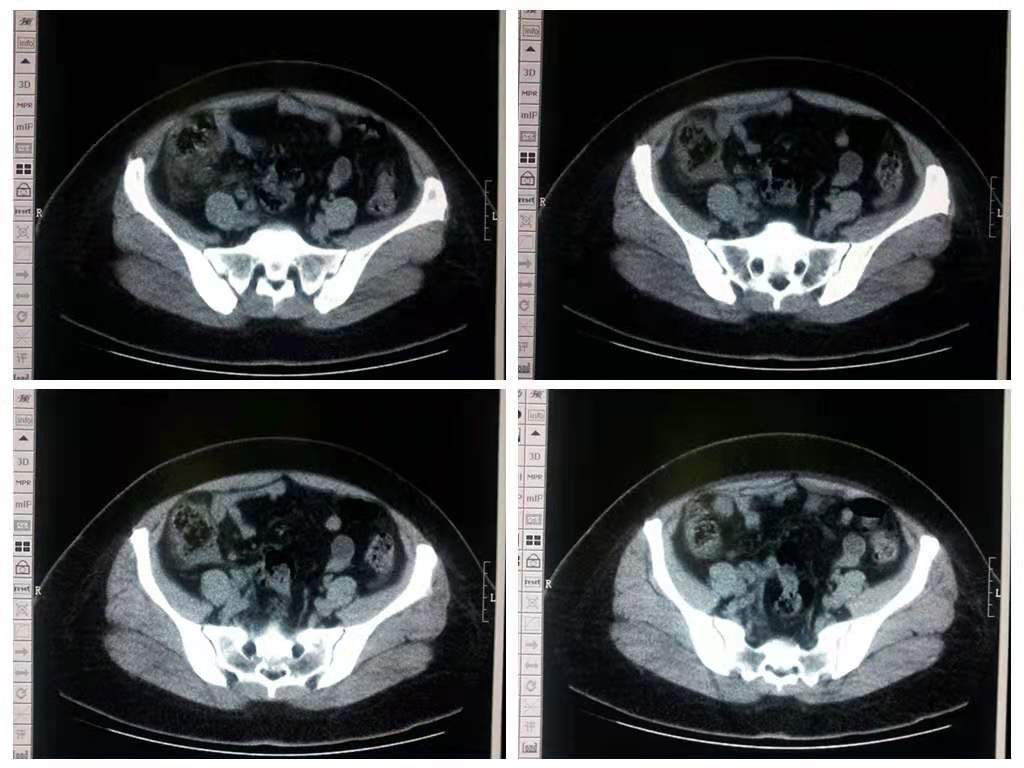

大多数高原病的诊断是临床症状,通常不需要实验室检查。高原肺水肿时低氧血症明显,经皮氧饱和度波动于40%~70%。取决于个体患病时的海拔高度。胸片提示心影大小正常和斑片状肺水肿。高原脑水肿通常可以通过病史及临床检查区别于其他原因造成的头痛和昏迷(如感染、脑出血、未控制的糖尿病);头部CT通常不需要做。